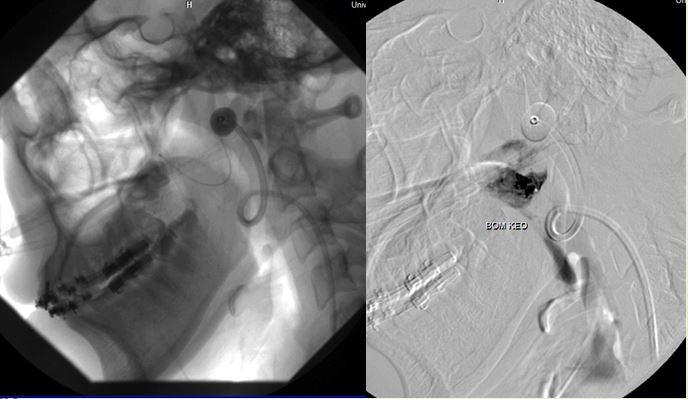

Nữ cựu chiến binh đã đi khám bệnh nhiều nơi vì mệt, siêu âm có giãn buồng tim, suy tim… Sau khi thăm khám tại các bệnh viện hàng đầu, hội chẩn nhiều chuyên khoa và với giáo sư nước ngoài… các chuyên gia đều nhận định là không thể phẫu thuật. Lý do là tĩnh mạch bao phủ cả vùng vai, đập dữ dội, nếu phẫu thuật bộc lộ ra cũng khó lòng tiếp cận được vị trí cần xử lý. Về nguyên lý đây cũng là một trường hợp thông động tĩnh mạch với lưu lượng lớn, BS Cường nhận thấy cần gây tắc tại điểm cuối cùng của động mạch và điểm đầu tiên của tĩnh mạch thì mới hiệu quả, tránh mạch máu bàng hệ tăng sinh. BS Cường vận dụng hết tất cả dụng cụ hiện có cho ca can thiệp khó khăn này, để chặn được động mạch dưới đòn lúc này đã giãn hơn 3cm, tiến hành đặt bóng và bơm keo (nếu đặt coil bệnh nhân sẽ tốn hơn 2 tỷ và coil có thể trôi về phổi, bệnh nhân sẽ tử vong). Rất may mắn, ca can thiệp đã thành công.

DSA can thiệp

Sau gây tắc